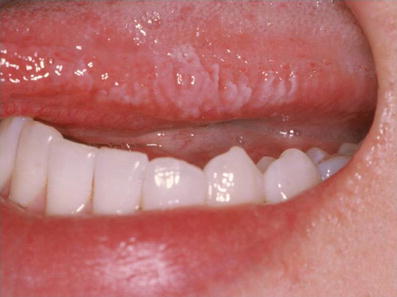

Hairy leukoplakia causes fuzzy, white patches that resemble folds or ridges, usually on the sides of your tongue . It's often mistaken for oral thrush, an infection marked by creamy white patches that can be wiped away, which is also common in people with a weakened immune system . When to see a doctor

Key points about oral hairy leukoplakia . Oral hairy leukoplakia is a condition triggered by the Epstein-Barr virus . It happens most often in people whose immune systems are very weak . It is most often seen in people with HIV . The condition causes white patches on the tongue . The patches can cause mild discomfort and taste changes .